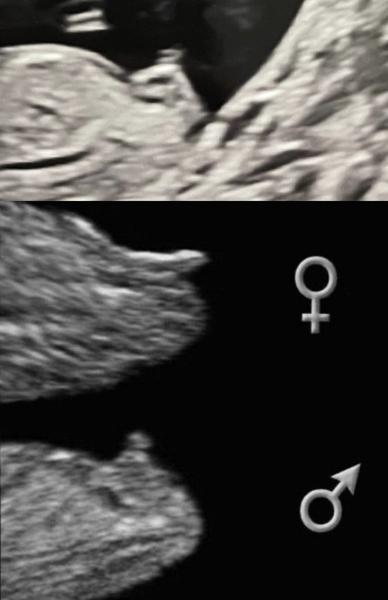

Tak co myslíte? Mám dvě fotky ze 13tt. Lékař mi svůj tip řekl - záměrně neprozrazuji! 🙂

Já to z tohoto nikdy nepoznám :D přijde mi, že hrbolek kouká dolů a je to holka...ale na druhém obrázku je nad tím zas něco..takže nevím, jsem marná. Já potřebuju ten pohled zespod 😀 ale tipla bych holku =)

Já bych podle první fotky řekla na 90% holka 🫣😁

Já tam vidím spis kluka.

@sishina podle 2 fotky si myslím chlapeček 😊. Tohle dcera na utz nemá 😅.

Tak je to zase 50 na 50 z fotky 12+0 to vypadalo na holku, dnes 12+4 na kluka. Tak jsme napnutý jako kšandy 🤣🤣🤣

Za mě kluk podle druhé fotky 🙂)